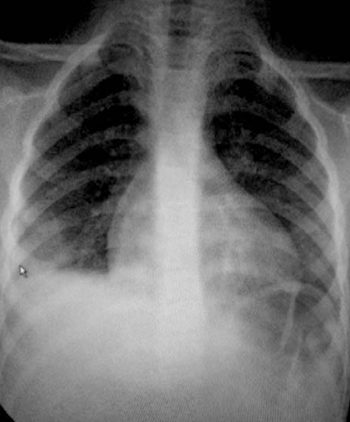

Se realizó radiografía de tórax (Figura 1) que informó opacidad homogénea de base de hemitórax derecho, con aumento de los espacios, con curva ascendente, compatible con derrame pleural y cardiomegalia.

Diagnóstico inicial: sepsis a punto de partida respiratorio. Neumonía de inicio agudo, comunitaria grave con derrame pleural. Se inicia tratamiento antibiótico y se traslada a cuidados intensivos (UCIP).